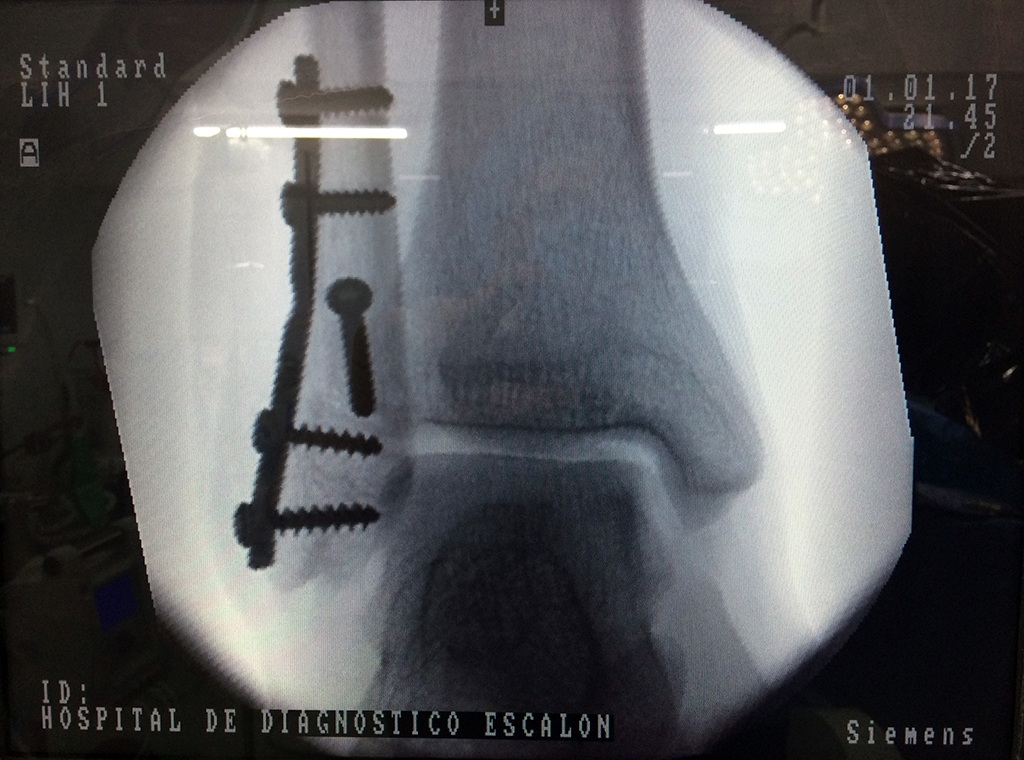

Cuando se necesita cirugía, es probable que esta implique el uso de clavijas de metal, tornillos o placas para sostener los huesos en su lugar mientras la fractura se consolida. Los elementos de soporte pueden ser temporales o permanentes.

Cirugía de Tobi...